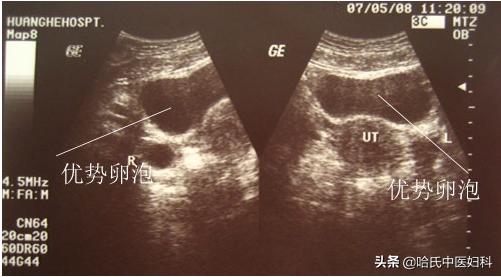

在排卵前卵泡处于生长期,由小变大,逐渐发展,如果按28天周期算,月经周期10天左右出现优势卵泡在12mm左右,然后以每天1.5-2.5mm的速度发展。

B超监测可以准确地看到卵泡的大小、发育情况并且预判排卵时间。一般于月经的第12天左右来院监测,根据卵泡发育情况医生会告知下次复查时间, 当卵泡大小在18-22mm则为成熟卵泡 ,排卵也就接近了,在观察到成熟卵泡后,建议再复查B超来观察卵泡是否已经排出。